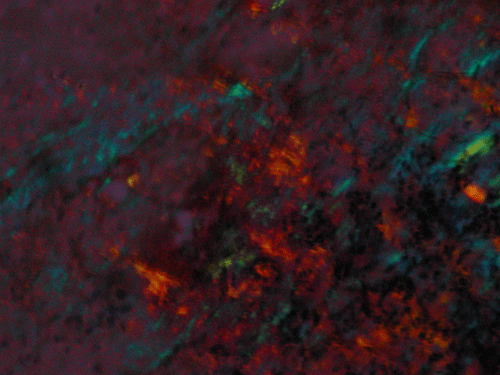

Clumps of amorphous substances with hypocellularity are noted with DiffQuick stain (arrows in Panel A) and Papanicolaou stain (arrows in Panel B). Normal glandular structures are also seen these preparations (Panel A and B). These amorphous substance stains orange on Congo red stain (Panel C and E) which gives a birefrigence under polarized light (Panel  D and F are corresponding images of Panel C and E). No tumor tissue is identified.

Amyloidosis is a broad designation for diseases characterized by the extracellular deposition and accumulation of amyloid. Amyloid is an insoluble protein with characteristic properties. It appears as non-branching fibrils with an average diameter of 10-12 nm. At the molecular level, the protein molecules arrange in a beta-pleated sheet conformation. This beta-pleated sheet is responsible for the distinctive apple green birefringence with Congo red stain 1. With routine hematoxylin-eosin stain, amyloid appears as pale eosinophilic, amorphous, extracellular deposition 1, 2.

Primary amyloidosis tends to involve the heart, gastrointestinal tract, nerves, skin, tongue, eye, and respiratory system. Secondary amyloidosis tends to involve the kidneys, liver, spleen, lymph nodes, adrenals, and thyroid. Symptomatic amyloidosis of the head and neck is a rare but well documented condition  3, 4, 5, 6, 7. Most cases in this region involve one organ, without evidence of generalized involvement. The cytologic diagnosis of unexpected amyloidosis in the head and neck region can be challenging. Amyloid can be misinterpreted as keratin debris, colloid, chondroid or basement membrane material. Salivary gland amyloidosis is most often secondary and can mimic Sjogren’s syndrome and also pleomorphic adenoma because of the amorphous appearance of amyloid. Amyloidosis involving the major salivary gland in the form of a mass is rather uncommon and often present as diffuse or focal, bilateral enlargement of salivary glands. Variable amounts of acellular, eosinophilic extracellular material stains pale red with Congo red stain, and exhibits a characteristic apple-green birefringence under polarized light. The remainder of the smear is often hypocellular, with scant or absent acinar cells, and scattered clusters of ductal epithelial cells such as are seen in chronic sialadenitis.